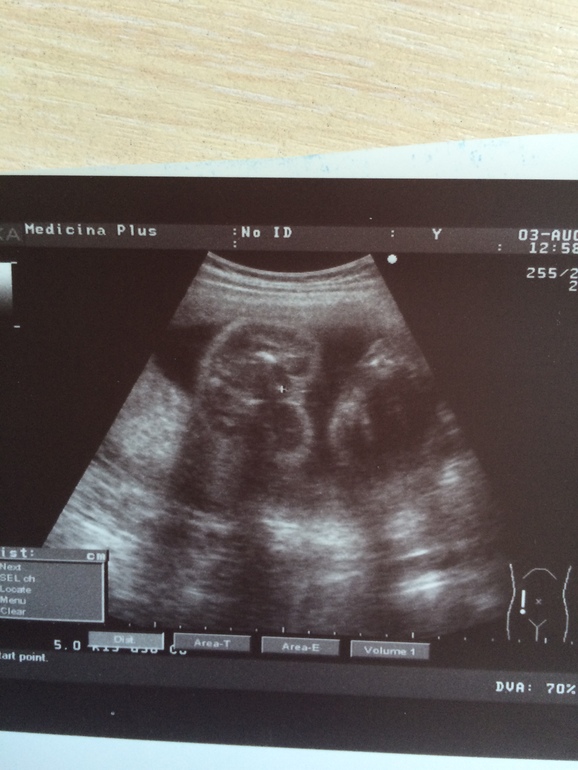

Пол малышаДевчоночки привет, за свои 25 недель делала УЗИ уже 7 раз, по показаниям естественно , и ни разу точно нам не говорили пол, был мальчик, девочка,( третьего не дано), потом не увидели,🙄(в19 недель), ну а вчера решила сходить для себя на УЗИ-месяц в деревне дался мне тяжко с младшеньким, да и 3000км на машине по нашим дорогам,в голове одни страхи за ребёнка , как он там??Слава богу все хорошо, соответствуем сроку , развиваемся, активно шевелимся, небольшой тонус, но не смертельно!Ну и заодно спросила кто там? Очень удивилась, что до сих пор не знаю и сказала ДЕВОЧКАААА! Ура 👏👏👏,два сыночка и дочка!! Сто раз переспросила, точно или нет?мне кажется поверю только в роддоме, сжеьала фото, девочки, там девчушка? Может кто понимает в этом что то